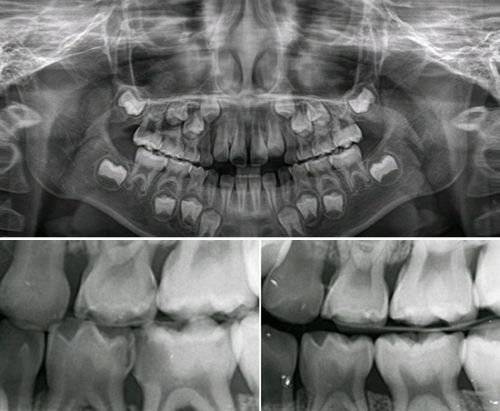

![구외 파노라마 방사선 검사 사진(위). 우식증이 있는 방사선 사진(아래). [자료 전승준]](https://img1.daumcdn.net/thumb/R658x0.q70/?fname=https://t1.daumcdn.net/news/202106/17/joongang/20210617110100855yymm.jpg)

그리고 이어지는 검사법이 치과용 방사선 검사입니다. 크게 구강 내 방사선 촬영술과 구강 외 방사선 촬영, 파노라마 방사선 촬영술이 있습니다. 이는 육안으로 확인되지 않는 치아 속 구조나 치조골 상태, 그 외 병리 상태를 찾아낼 수 있다는 점에서 치과 치료에 필수적입니다. 하지만 방사선이 몸에 해로울 수 있다는 것에 대해 부담감을 가지고 계신 환자도 있는 것이 현실입니다. 하지만 치과용 방사선은 안전합니다. 평소에 우리 주위의 야외에도 방사선이 존재한다는 것을 아시는 분은 많지 않습니다. 진단을 위해 구내 치근단 방사선 1장 촬영 시의 방사선량은 일상생활 중 자연에서 무심코 하루 동안에 받는 양 정도입니다. 그나마도 줄이기 위해 촬영 시 납방어복으로 보호하고 촬영을 하므로 안심하고 검사를 받으셔도 됩니다.